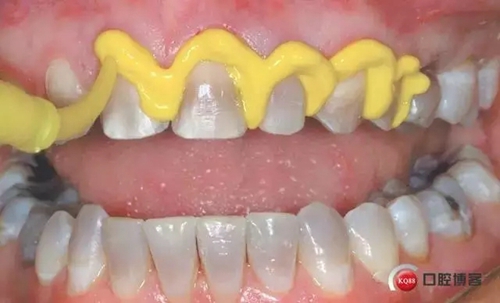

5. 放置第二根排齦線:選擇一根可以填滿牙齦溝的排齦線。可以觀察到排齦線完全包繞牙體。第二根排齦線往往需要浸漬止血材料: 如果是通透性好的牙冠(二硅酸鋰)選擇氯化鋁止血材料;如果是不透明的冠(金屬冠/烤瓷冠)則選擇和硫酸鐵。注意: 盡管硫酸鐵有效,但是硫酸鐵可以使基牙染色,并可以使通透性好的牙冠透色。

1498612885_827290.jpg